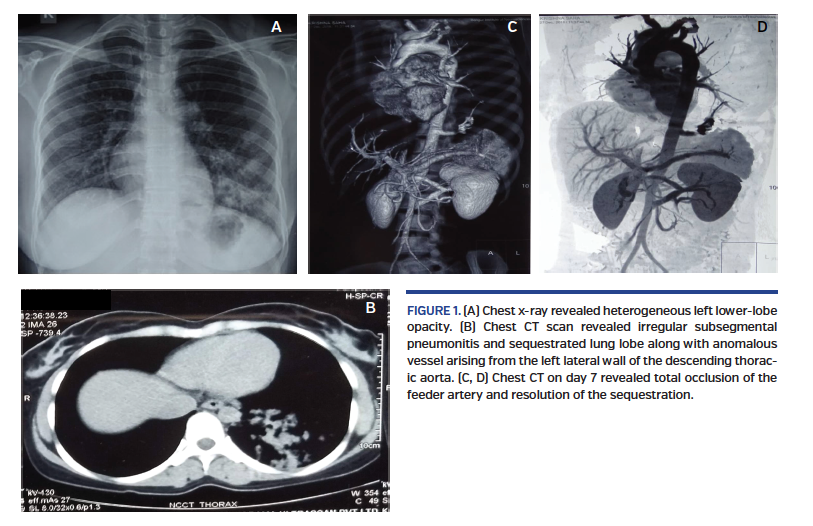

A 25-year old woman presented with recurrent chest infections since childhood. She had been experiencing increased frequency of infections and hemoptysis for 1 year and had received multiple courses of antibiotics. Physical examination revealed mild pallor. Routine blood investigations revealed a hemoglobin of 7.8 g/dL with normal kidney and liver function tests. A chest x-ray revealed heterogeneous left lower-lobe opacity (Figure 1A). Computed tomography (CT) scan of the chest revealed irregular subsegmental pneumonitis in the posterior basal segment of the left lower zone, with sequestrated lung lobe along with anomalous vessel arising from the left lateral wall of the descending thoracic aorta (Figure 2). An aortogram with selective dye injection identified the feeder vessel (Video 1).

An informed decision was made for percutaneous closure of the feeder vessel using an Amplatzer vascular plug (St. Jude Medical). The feeder was occluded and was seen to be thrombosed on cine angio scans (Video 2). The patient’s postoperative course involved chest pain on day 2, which was managed with opiates. However, she remained hemodynamically stable throughout. A chest CT on day 7 revealed total occlusion of the feeder artery and resolution of the sequestration (Figure 3).